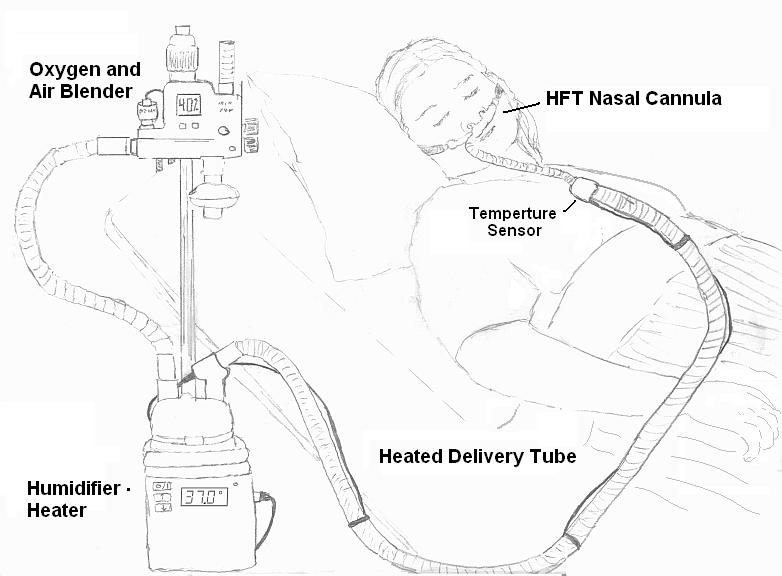

- High flow nasal cannulae – consists of wider – bore prongs and offers humidification and titration of oxygen concentrations to be delivered.